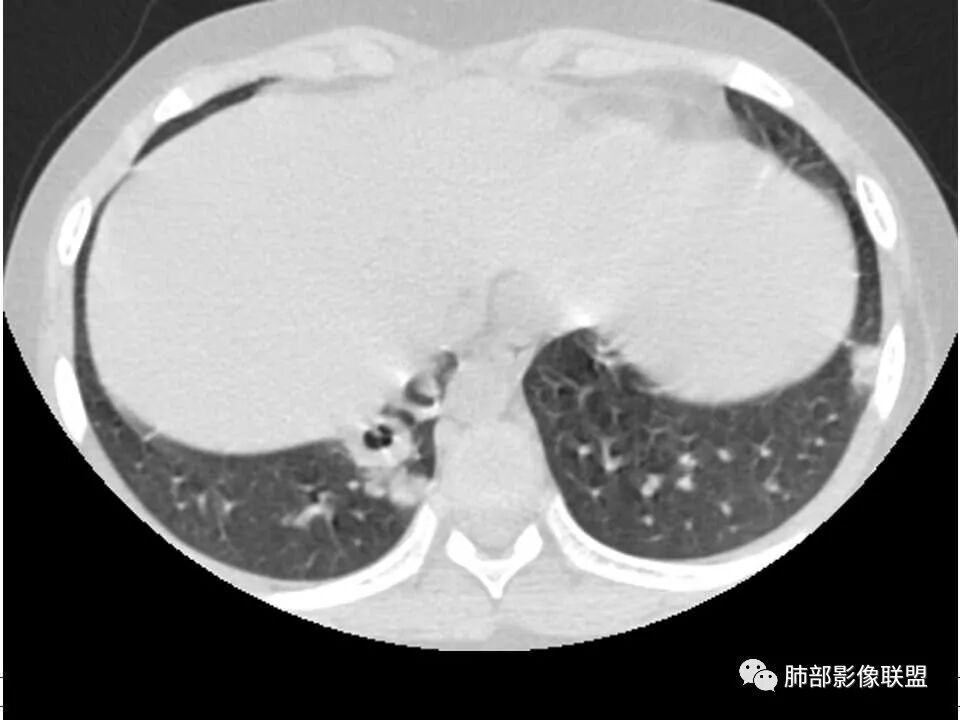

患者儿童,因右下肢疼痛伴肿胀14天就诊。病程中有发热及伴随症状。膝关节MRI提示右侧膝关节及右髌骨髁异常信号影,右膝髌上囊及关节腔内少量积液。胸部CT:双肺胸膜下多发结节影,部分结节空洞形成,且结节周围可见血管集束征。综合考虑血源性脓毒性肺栓塞、坏死性肺炎。右侧骨髓炎、血播性金葡菌肺炎,鉴别其他特殊感染及血管炎。

发热,下肢肿胀骨髓水肿,骨髓炎可能;双肺多发结节,部分空洞,左下肺胸膜下楔形阴影,考虑感染性病变,肺梗死;上腔静脉、奇静脉增宽,肝大,考虑股部深静脉拴子进入体循环及肺动脉,综上考虑下肢骨髓炎,深静脉脓毒栓子,肺部感染并肺栓塞

男,8岁,两肺多发随机分布结节空洞影,壁光整,考虑血道来源,结合右侧膝关节有骨髓水肿信号,临床感染指标明显增高,考虑骨髓炎并血道播散,金葡菌感染?LCH小孩骨头症状相对较轻,放在代排吧。

小儿,急性起病,下肢疼痛,mr提示骨髓水肿,临床化验炎性指标高,考虑金葡菌骨髓炎,双肺多发结节,以血管支气管束及胸膜下分布为主,部分结节近端与血管相连,部分结节可见空腔,内壁光整,部分囊腔有张力,考虑骨髓炎并肺内血播感染,金葡?

儿童,发热,急性起病,右下肢骨水肿,两肺弥漫性病变,伴囊,胸膜下分布,部分呈楔形,血道分布,符合金葡菌感染,脓毒肺栓塞

2.双肺多发片影,随机分布,多空洞或囊腔,胸膜下多楔形影,气道未见受累等等符合脓毒血症影像学表现,尤其是金葡。